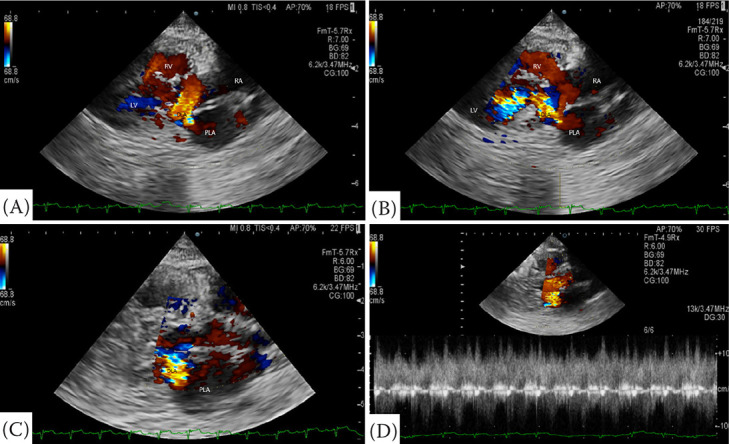

一只6岁的雌性绝育土耳其安哥拉猫因呼吸急促而被转诊。该患者两年前在当地医院进行健康检查时被诊断为心脏肥大。呼吸急促发生在一年前。体格检查时,患者呼吸频率为每分钟72次,收缩压为70 mmHg。胸片显示严重的心脏肥大,左心房(LA)增大,右心房(RA)增大,右心室增大,肺动脉和肺静脉扩张。在右、左颅肺叶可见肺泡型。超声心动图显示一层膜将左心室分为两个腔室,下房间隔缺损,前或后三尖瓣(TV)伸长。然而,没有观察到间隔电视。在心脏收缩期,经房间隔缺损证实血流量从左心房流向右心房。舒张期,血流量从左室到左室被证实。这些结果提示心房三房性心绞痛(CTS)合并部分房室间隔缺损(AVSD)。本报告描述了超声心动图诊断CTS合并部分AVSD的猫。

A 6-year-old female neutered Turkish Angora cat was referred due to tachypnoea. The patient was diagnosed with cardiomegaly at a local hospital during a health screening two years ago. Tachypnoea occurred one year ago. On physical examination, the patient presented with a respiratory rate of 72 breaths per minute and a systolic blood pressure of 70 mmHg. Thoracic radiographs revealed severe cardiomegaly, left atrium (LA) enlargement, right atrium (RA) enlargement, right ventricular enlargement, and dilation of pulmonary arteries and veins. An alveolar pattern was identified in the right and left cranial lung lobes. Echocardiography revealed a membrane that divided the LA into two chambers, a defect in the lower atrial septum, and elongation of anterior or posterior tricuspid valves (TV). However, septal TV was not observed. During systole, blood flow from LA to RA was confirmed through a defect in the atrial septum. During diastole, blood flow from LA to left ventricular was confirmed. These findings suggest cor triatriatum sinister (CTS) with partial atrioventricular septal defect (AVSD). This report describes echocardiographic diagnosis of CTS with partial AVSD in a cat.